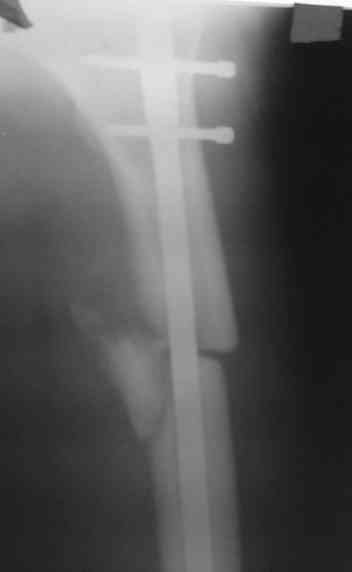

> денамизация - февраль 2006. ( 3 и 4 снимки) на сегодняшний день (снимок 5) беспокоит боли в тбс...

Однозначно: удалить, рассверлить, перештифтовать более толстым гвоздем. ЭТОТ 9 мм будет? Возьмите 12-14.

Дистально обязательно два винта! Проксимально можно один динамический. Больной будет счастлив на следующий же день!

Учитывая точку введения - верхушка б\вертела - что бы исправить варус взял бы соответствующий гвоздь: длинную Гамму или PFN или Recon